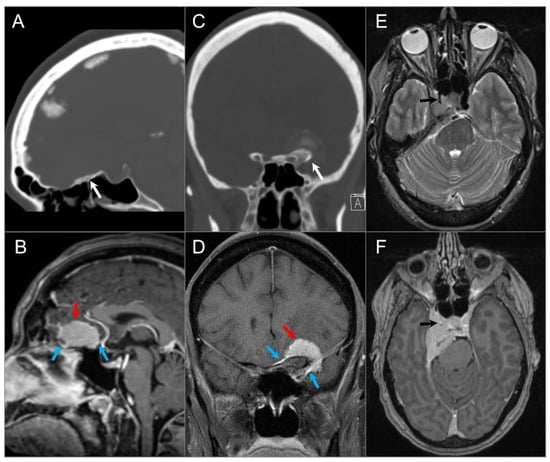

4.3.3. Langerhans Cell Histiocytosis

4.3.4. Cholesterol Granuloma